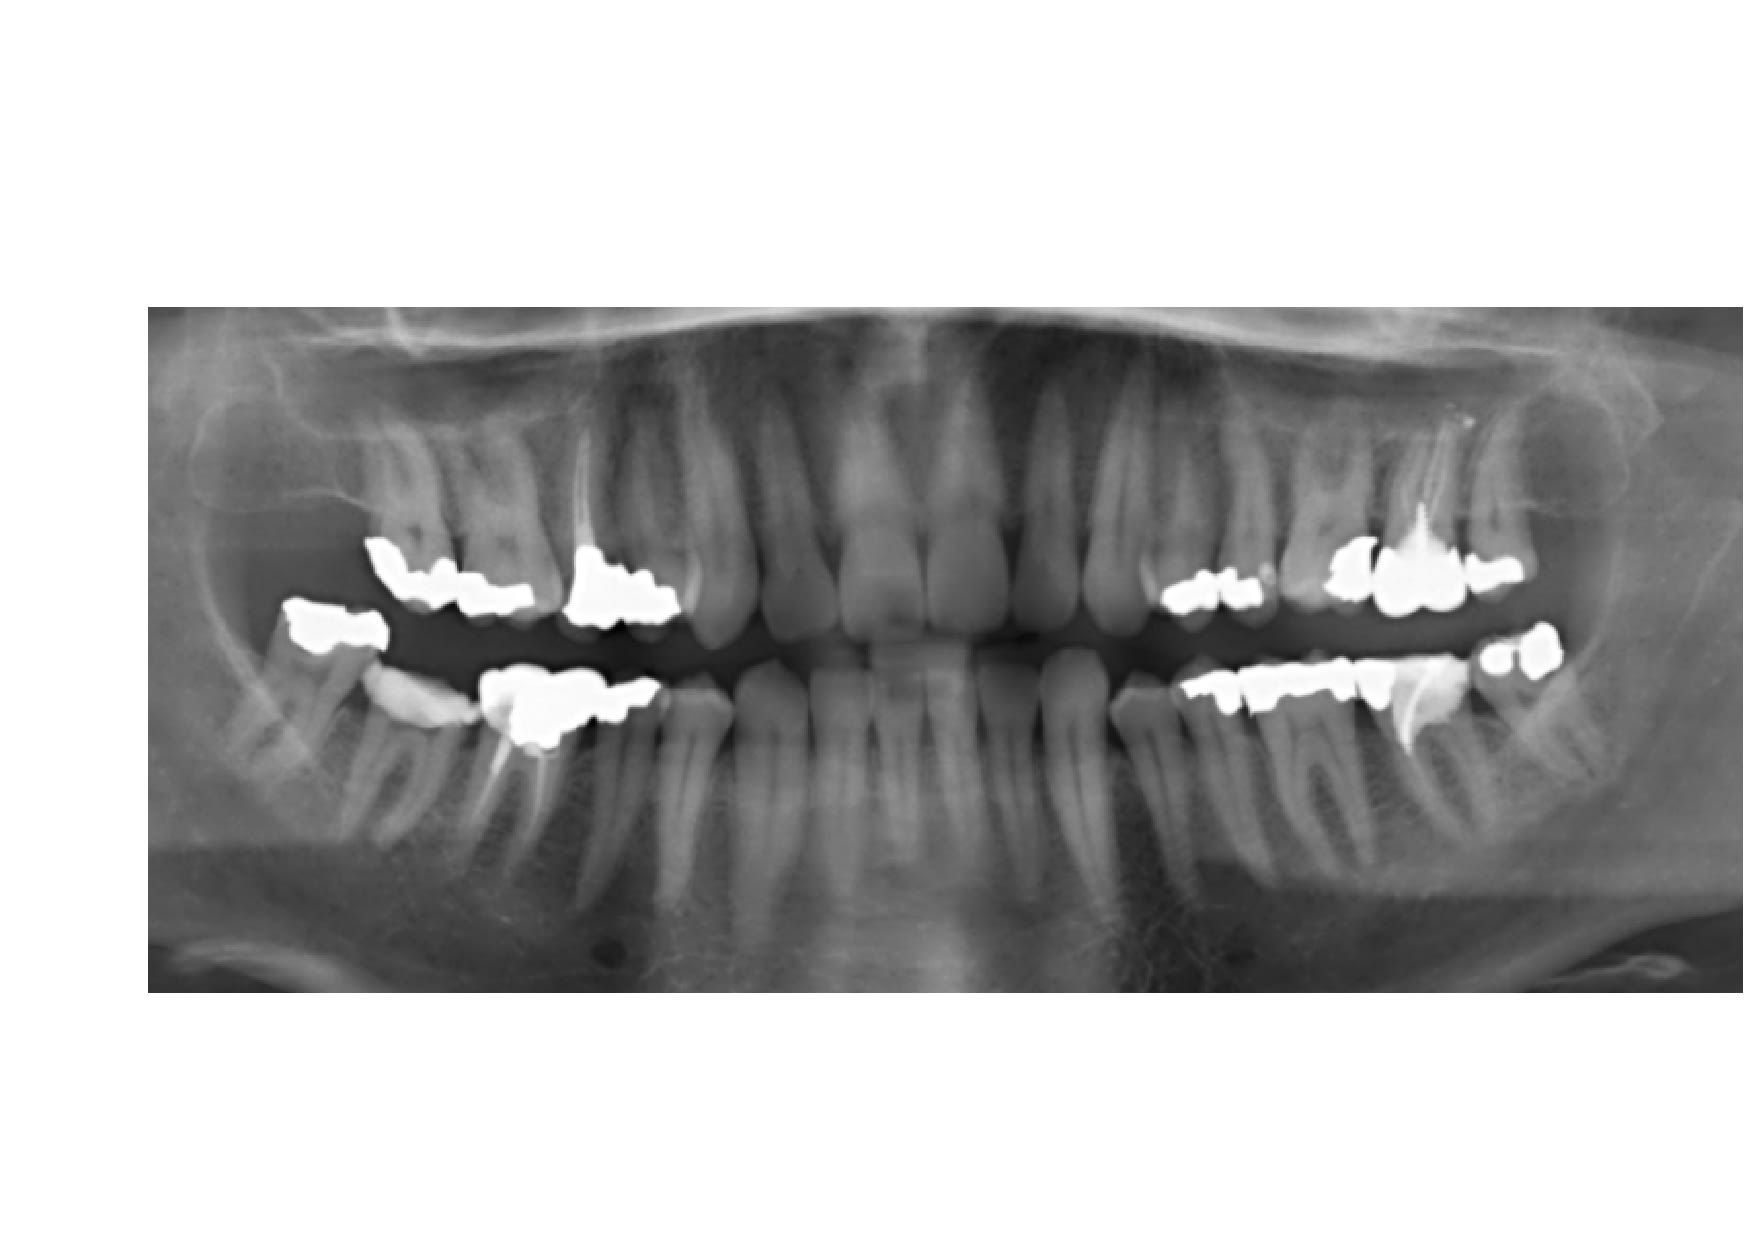

Voir pano en PJ.

La radiographie panoramique semble ancienne, la couronne au niveau de la 27 à t elle été changée ou retouchée ?

N'avez vous pas une pano plus récente car avec cette couronne qui ensemble sortir de l'arcade il est possible que le pression qui en résulte de manière antero postérieur sur les 37 36 engendre certaine douleur avec aussi possibilité de douleurs du niveau des dents anterieures

Pourquoi pas de cone beam ? On pourrait voir plein de choses, notamment si la 37 a été traitée correctement c'est pas top en mésial et peut-être qu'1 canal a été oublié j'ai l'impression qu'un seul a été obturé.